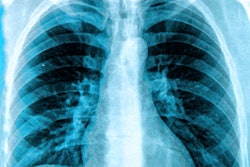

An artificial intelligence (AI) algorithm can automatically analyze pediatric x-rays to identify patients with incorrectly positioned catheters, potentially enabling these studies to be triaged for priority review by radiologists, according to research published online April 10 in the Journal of Digital Imaging.

Catheters and tubes are commonly used during management of neonates who are critically ill or have low birth weight. However, these catheters are typically placed without real-time image guidance and are frequently malpositioned, which may result in serious complications, according to the researchers.

Researchers trained a deep-learning algorithm to detect and assess the placement of all commonly seen catheters on pediatric x-rays by generating synthetic catheters on a random selection of 2,515 frontal-view images, which came from the U.S. National Institutes of Health Open-i adult chest x-ray dataset. Yi and colleagues then tested the algorithm on a dataset comprised of frontal chest/abdominal x-rays gathered at their institution on patients less than 4 weeks old. The test set included 35 images with different catheter types.